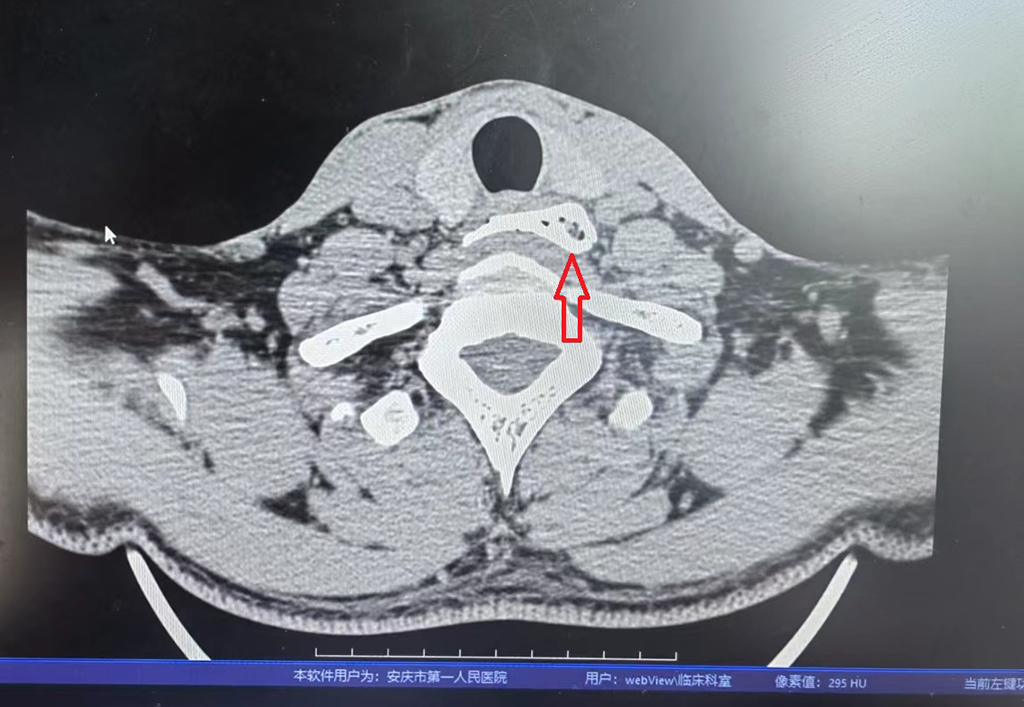

食管轴位CT影像(箭头所指为食管异物影像)

当天,陈先生的母亲为其煮了一碗螺蛳粉,因不知晓这碗螺蛳粉是用骨头汤煮的,粗心的陈先生误吞下一块“巨型”猪骨头。这块猪骨呈长方形,长约4.1cm,宽约3.8 cm,厚度约3mm,四角尖锐,正好卡在食管入口的下方。入院时,患者十分痛苦,说话困难,连口水都无法吞咽,并且“巨型”骨尖锐锋利的边角随时都有穿通食管的可能,一旦造成食管穿孔并发感染,陈先生将会面临生命危险。